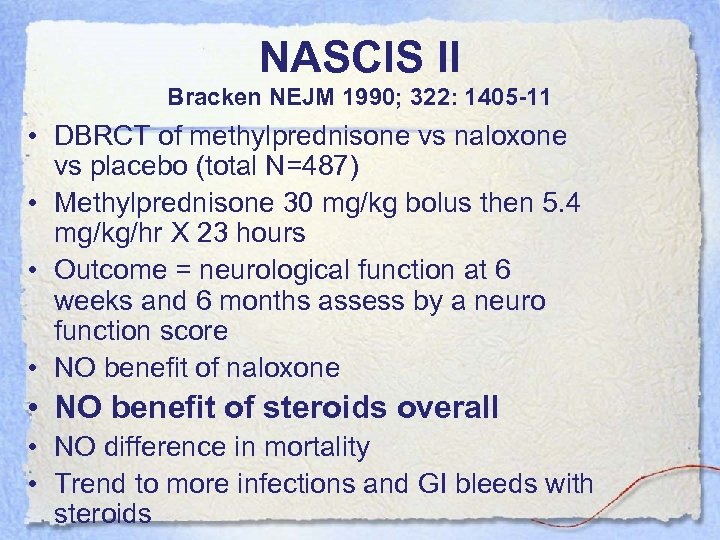

NASCIS II Bracken NEJM 1990; 322: 1405 -11 • DBRCT of methylprednisone vs naloxone vs placebo (total N=487) • Methylprednisone 30 mg/kg bolus then 5. 4 mg/kg/hr X 23 hours • Outcome = neurological function at 6 weeks and 6 months assess by a neuro function score • NO benefit of naloxone • NO benefit of steroids overall • NO difference in mortality • Trend to more infections and GI bleeds with steroids

NASCIS II Bracken NEJM 1990; 322: 1405 -11 • DBRCT of methylprednisone vs naloxone vs placebo (total N=487) • Methylprednisone 30 mg/kg bolus then 5. 4 mg/kg/hr X 23 hours • Outcome = neurological function at 6 weeks and 6 months assess by a neuro function score • NO benefit of naloxone • NO benefit of steroids overall • NO difference in mortality • Trend to more infections and GI bleeds with steroids